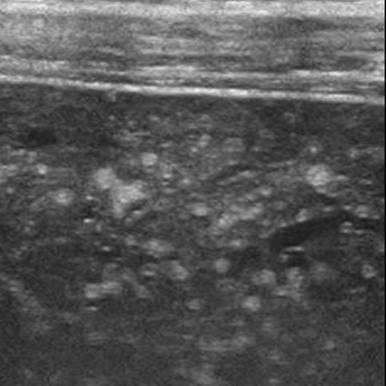

Hamartoma đường mật

» Thông tin: Nam giới – 34 tuổi.

» Lâm sàng: Kiểm tra sức khỏe.